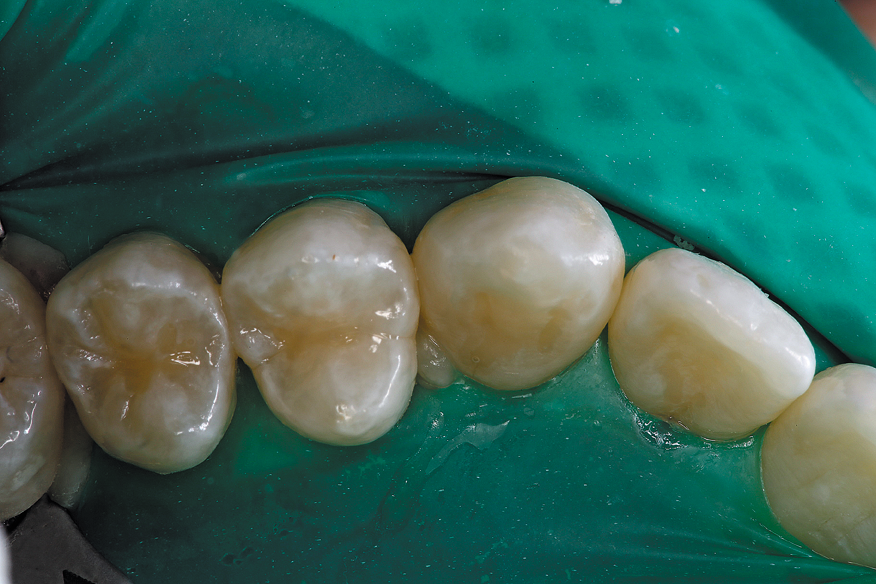

The patient was happy the carious tooth was restored in an efficient manner with zero discomfort and that a vast majority of healthy tooth structure was maintained (Fig. 3).

The combination of innovations in rotary instrumentation and resin materials allows clinicians to provide minimal intervention with maximum effectiveness.